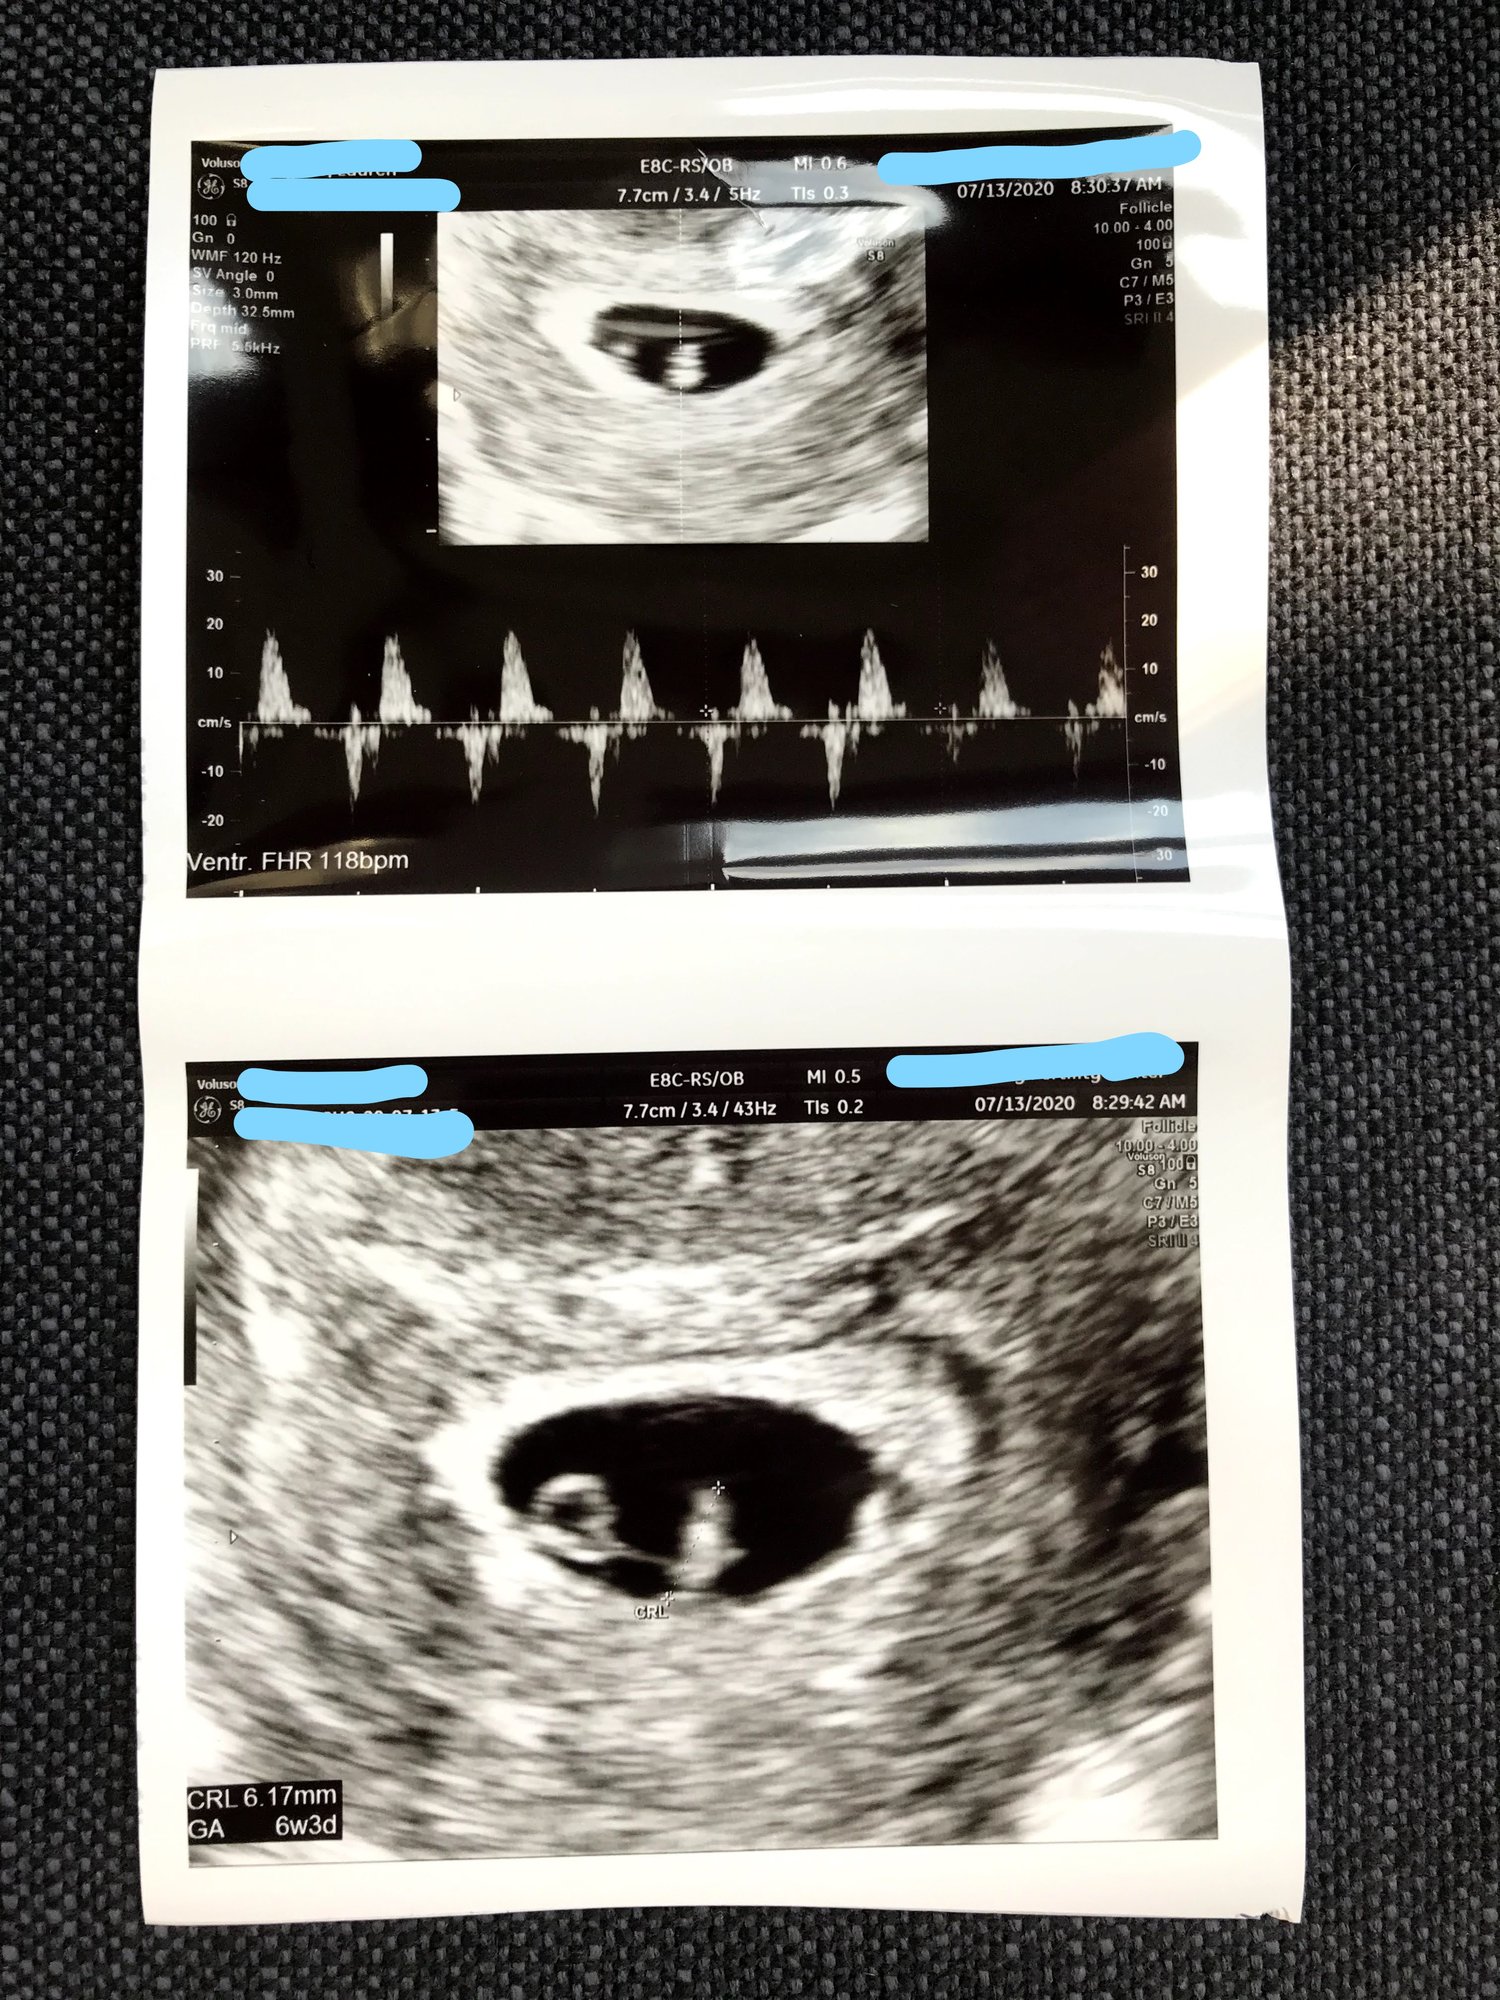

• Update: there is a baby in there with a strong heartbeat measuring right on time to my due date. Adjusted due date is March 6, 2021 because it’s based on the FET date not lmp (had no idea)! Feeling at ease! My clinic released patience after the heartbeat is seen and heard (which is was 🙌🏻) so I have an exit call with them this afternoon to determine weaning schedule for progesterone and estrogen. First appointment with OBGYN is 7/27!